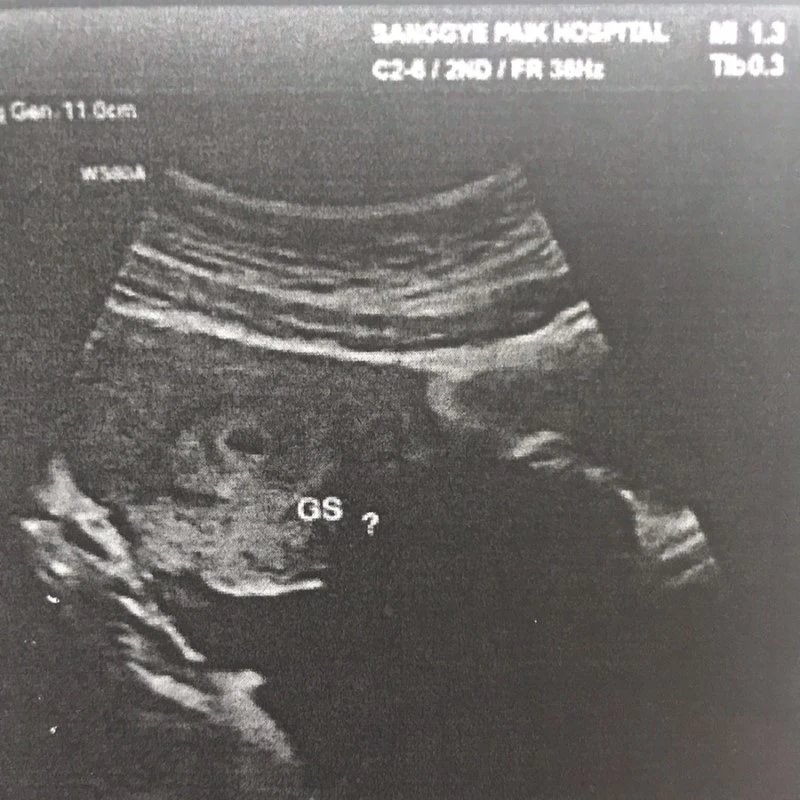

초음파 선생님이 열심히 봐주셨는데 이놈에 아기집은 딱 보이지 않았다. 나에게 주먹으로 허리를 받치고 있어 보라 하셨다. 자궁각.. 자궁외.. 포상기태... 내 머릿속에는 여러 단어가 흘러지나 갔다. 한참을 보시다 어, 이건가? 하시며 그늘진 한 구석에서 동그란 무언가를 발견하셨다. 안쪽에 어두워서 잘 보이지 않는다시며 선생님은 배초음파로 바꾸셨다. 배를 꾹꾹 눌러가며 동그라미를 찾으신 선생님은 아직 작아서 확실치는 않다시며 GS(아기집) 옆에 ?물음표를 붙이셨다. 크기는 0.6cm 정도..

찾았다 요놈!